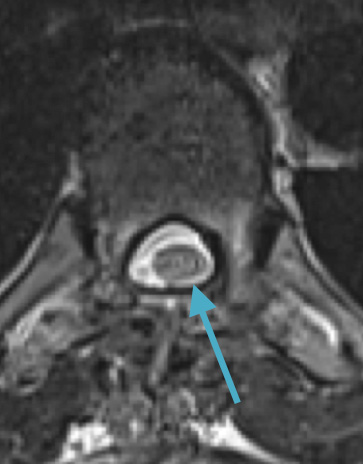

Postoperative MRI T1w demonstrating interval resection with cord re-expansion (blue arrow)

Postoperative MRI T2 illustrating the restoration of CSF surrounding the cord (blue arrow)